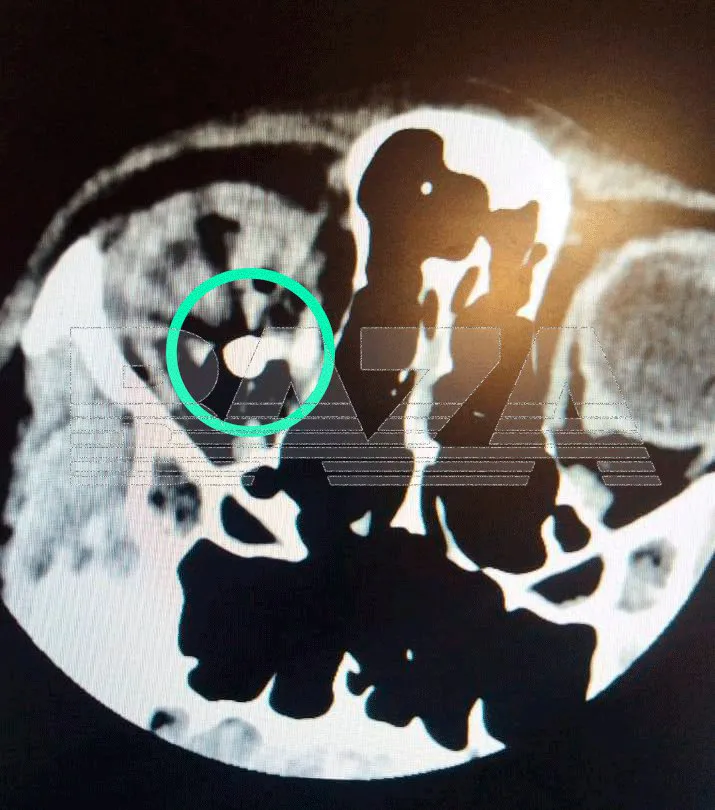

Пуля пробила глазное яблоко и застряла в черепе мальчика на глубине 7 миллиметров. Медики до сих пор не могут извлечь её. Спасти пострадавший глаз, к сожалению, уже не удастся.

Фото: Baza